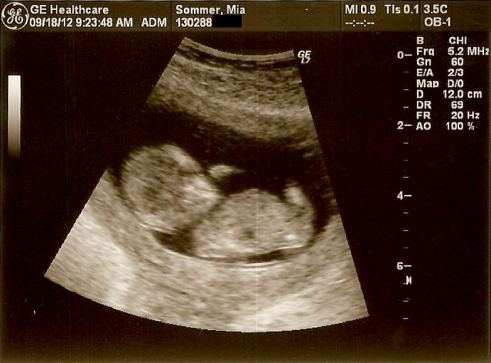

I øvrigt har jeg en god nyhed, som jeg vil dele med mine læsere. Jeg er gravid og venter mit andet barn. Det nederste billede er fra nakkefoldsscanningen i dag 🙂 Jeg er meget glad og har det fantastisk i min graviditet! Jeg har slet ikke kvalme, så der er ingen undskyldning for ikke at spise en masse lækker og sund mad. Jeg har dog forsømt min blog de sidste par måneder pga. mangel på energi og motivation, og med både studie, arbejde og søn skal jeg ikke kunne sige, hvor ofte indlæggene kommer dumpende fremover. Men energien og motivationen er i hvert fald tilbage, så må vi se, hvad der bliver tid til 🙂